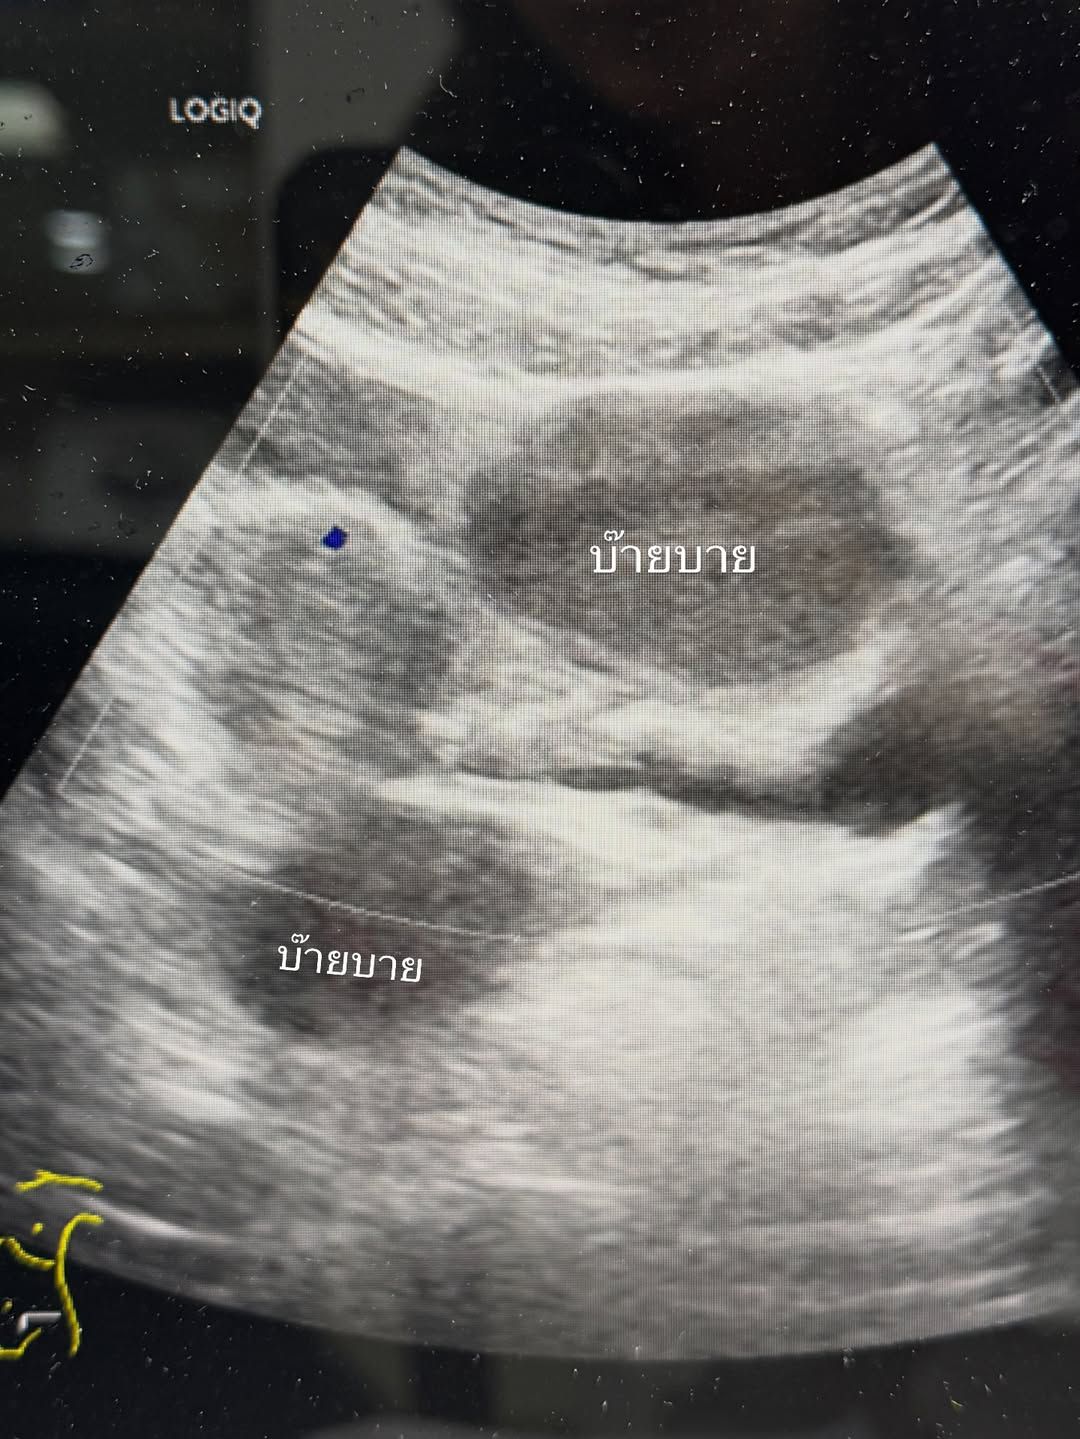

จ๊ะจ๋าเผยผ่านแคปชั่นว่า การเข้าโรงพยาบาลครั้งนี้เกิดจากการไปอัลตราซาวด์แล้วพบ ช็อกโกแลตซีสต์ถึง 2 ลูก ซึ่งเป็นถุงน้ำรังไข่ที่เกิดจากเยื่อบุโพรงมดลูกเจริญผิดที่ โดยขนาดของมันใหญ่เกินกว่าที่จะรักษาด้วยการทานยาให้ยุบได้ คุณหมอจึงตัดสินใจให้ทำการผ่าตัดทันที

โชคยังดีที่ขนาดของซีสต์ยังไม่ใหญ่จนถึงขั้นต้องผ่าเปิดหน้าท้อง คุณหมอจึงใช้วิธี "ผ่าตัดส่องกล้อง" ซึ่งช่วยให้แผลเล็กและเจ็บน้อยกว่า